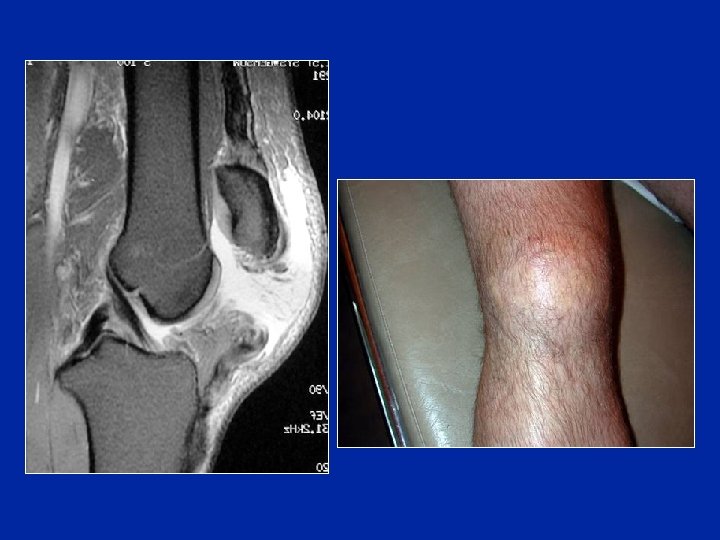

Ruptura del tendón cuadricipital ignorada

Ruptura del tendón cuadricipital ignorada Calcificaciones en la cima de la rótula